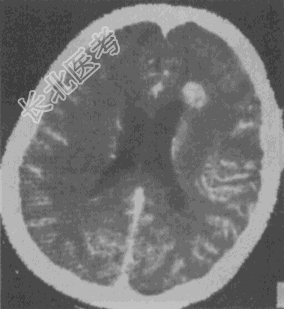

- 单项选择题女性,40岁。CT发现额叶异常密度灶, 无任何症状及体征。CT诊断(见图)最大可能是

A、正常钙化灶

B、脑膜瘤

C、少突胶质细胞瘤

D、海绵状血管瘤

E、脑出血